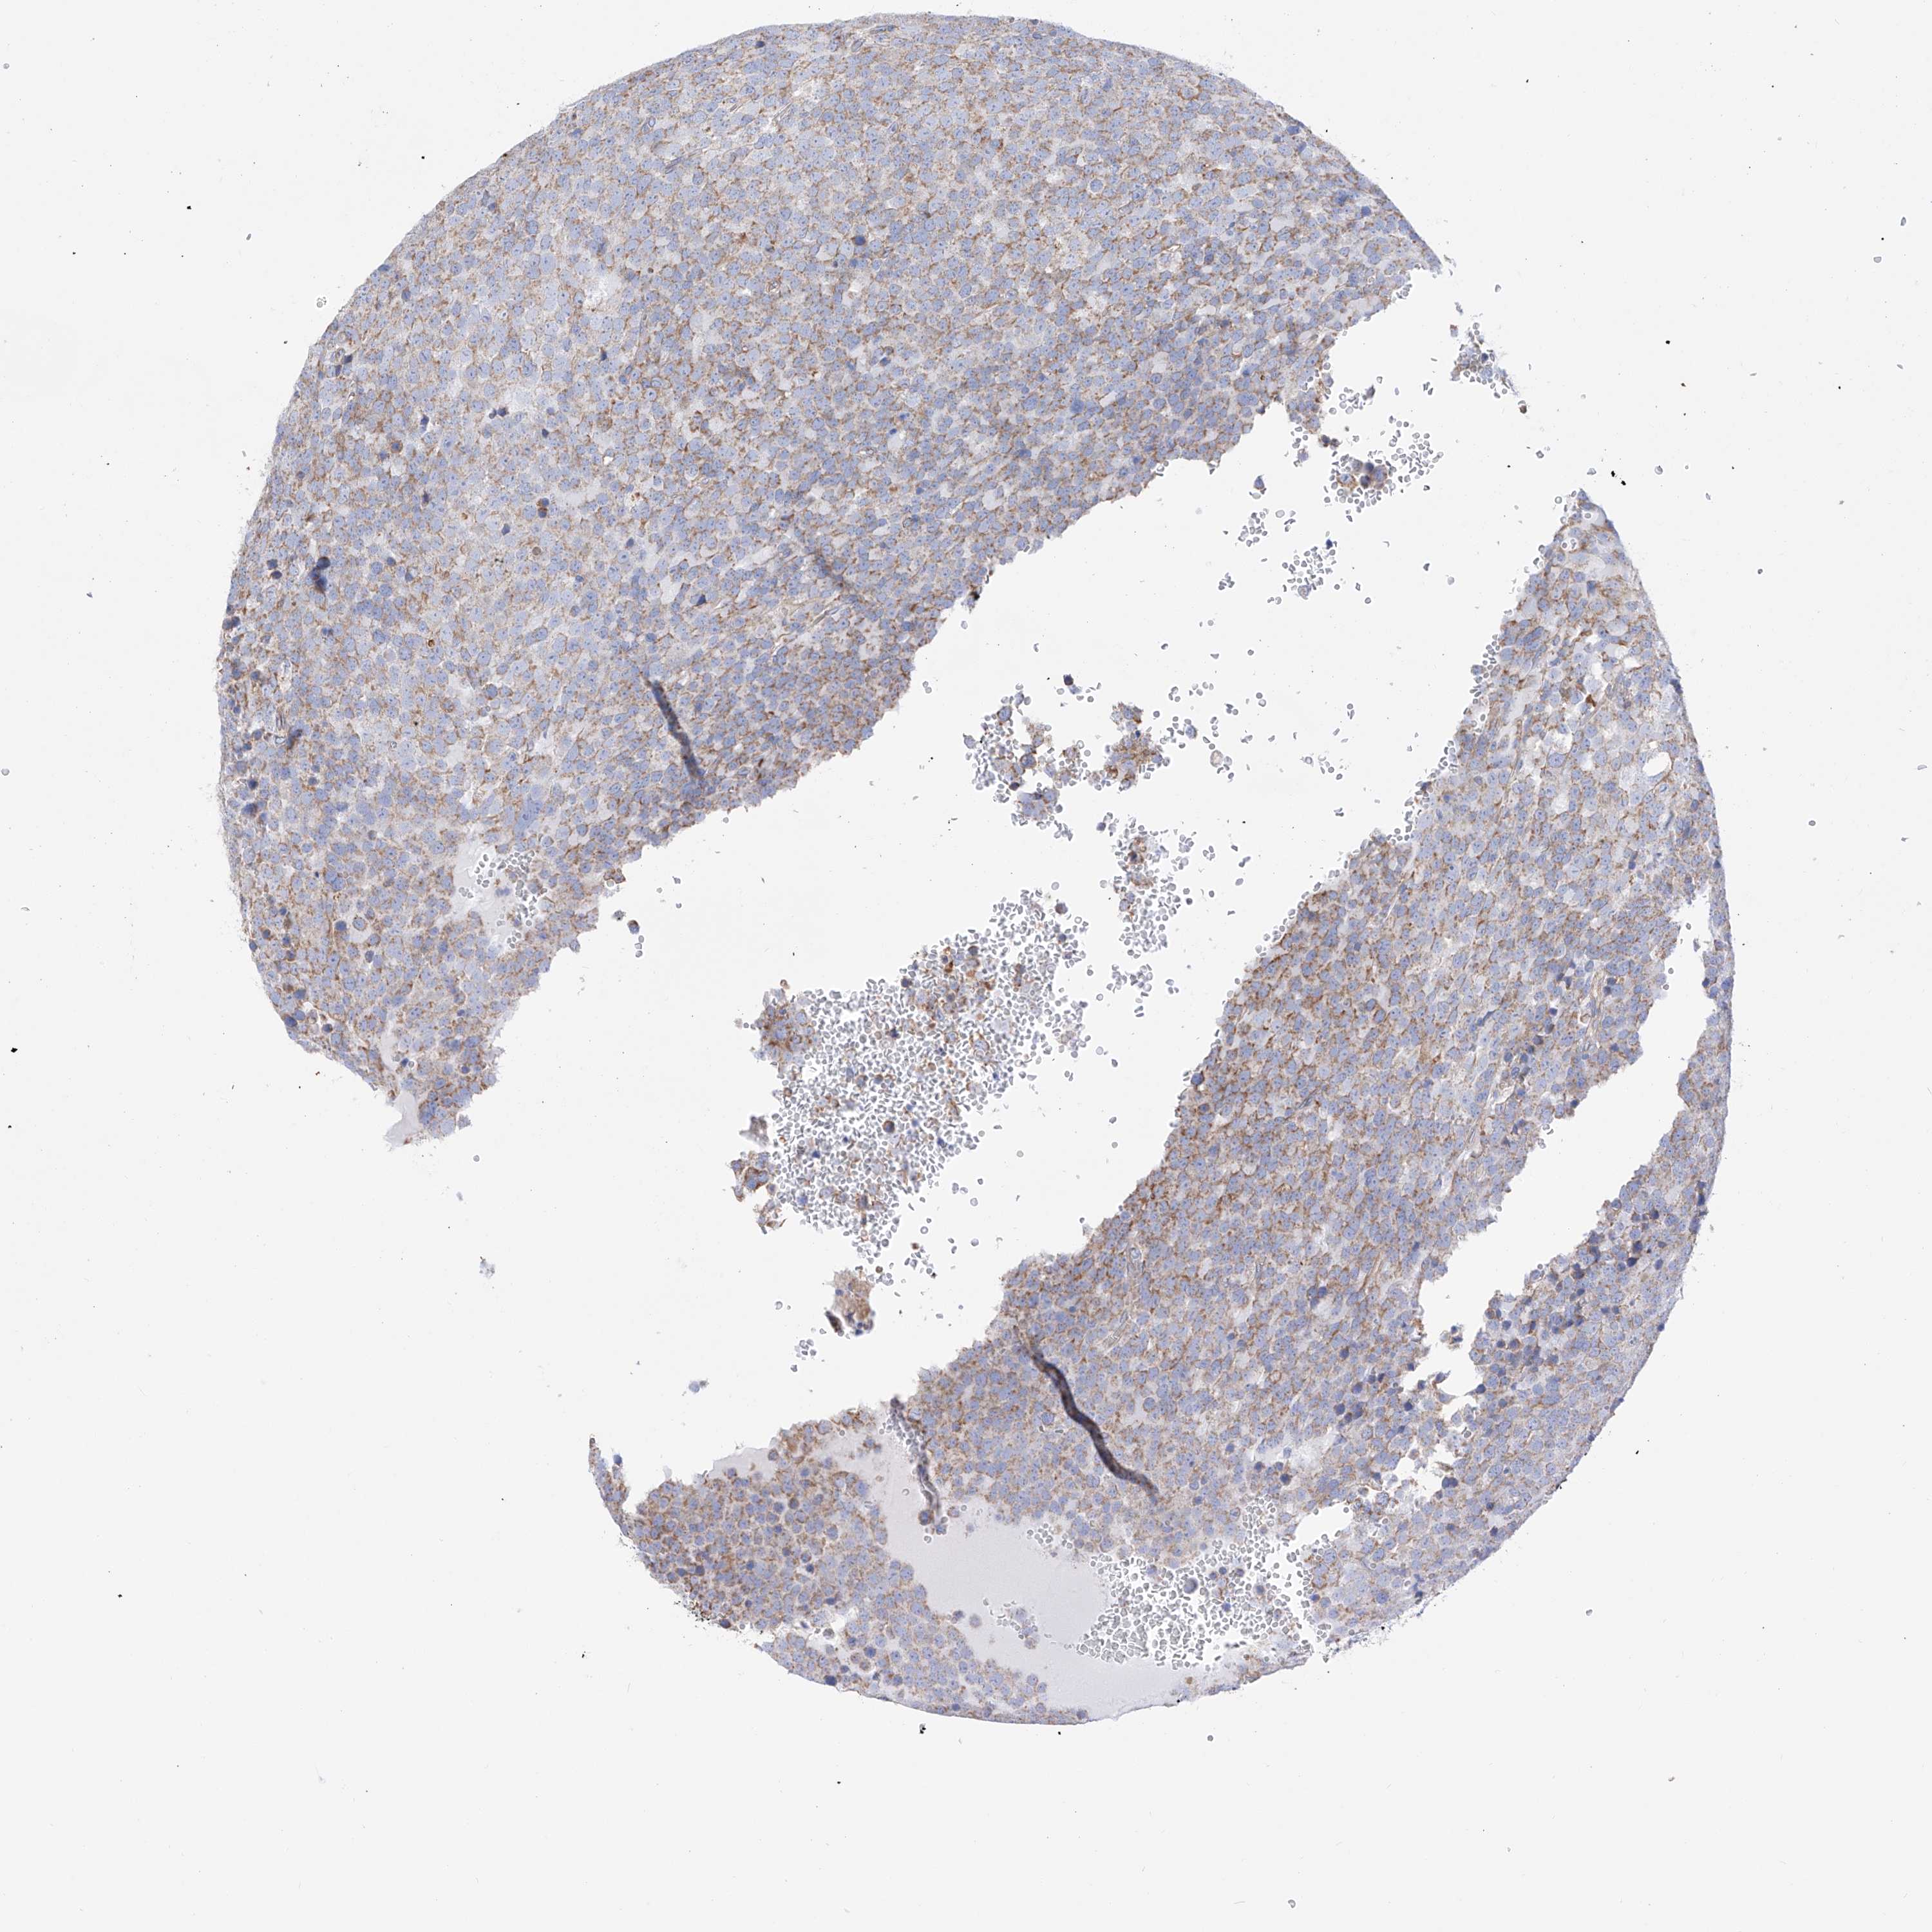

TESTIS CANCER - Protein expressioni

A mouse-over function shows sample information and annotation data. Click on an image to view it in a full screen mode. Samples can be filtered based on level of antibody staining by selecting one or several of the following categories: high, medium, low and not detected. The assay and annotation is described here.

Note that samples used for immunohistochemistry by the Human Protein Atlas do not correspond to samples in the TCGA dataset.

Antibody stainingi

Antibody staining in the annotated cell types in the current human tissue is reported as not detected, low, medium, or high, based on conventional immunohistochemistry profiling in selected tissues. This score is based on the combination of the staining intensity and fraction of stained cells.

Each image is clickable and will lead to virtual microscopy that enables deeper exploration of all samples and also displays staining intensity scores, fraction scores and subcellular localization as well as patient and tissue information for each sample.

Antibody HPA030188

Antibody CAB002210

Carcinoma, Embryonal, NOS

Seminoma, NOS